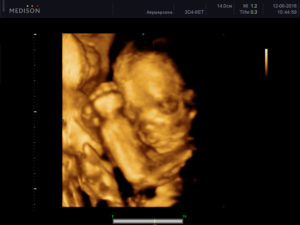

В предыдущую беременность делали 3Д на 19 и 32 неделях) на 19 еще похож был на инопланетянина)) а вот на 32 отлично видно было все черты лица) в эту беременность включили 3Д на первом скрининге, 12 недель, совсем жутковато пока))

в 18-19 они там еще такие страшненькие... мы были в 27 недель.. от макушки до коленок на весь экран был.. весь виден.. вот после 34 недель будет или голова или спина или ну вы поняли только на весь экран... первая 19 вторая третья 27

в 18-19 правда рановато для 3д, они страшненькие еще) у нас скрининг второй был в 21 неделю ровно, 3д и тоже еще так себе я вам скажу фоточки)))))))